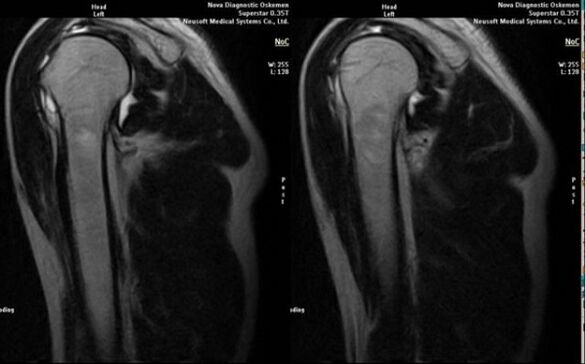

- magnetic resonance and computed tomography;

Signs indicating the development of osteoarthritis directly include the appearance of significant narrowing of the joint space, sclerosis of subcartilaginous structures, thinning of the chondrocyte layer itself, the appearance of osteophytes and deposition of salt crystals in the intra-articular fluid.